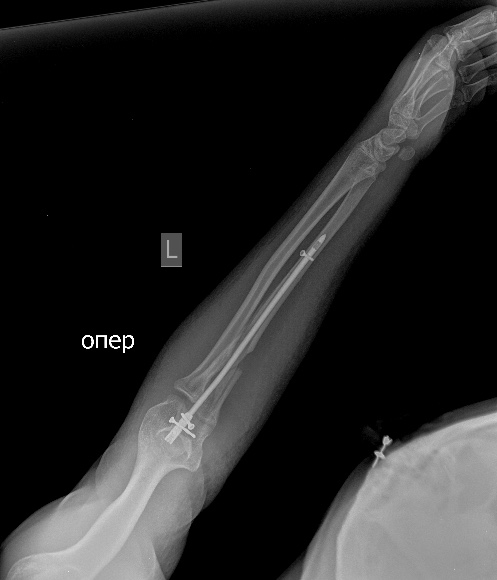

[Ortho] псевдоартроз локтевой с застарелым вывихом радиоульнарного сочленения

Мы бы удалили пластину.  Аппаратом постепенно восстановили бы

взаимоотношения. И заштифтовали бы локтевую кость, смоделировав

стержень, чтобы он был напряжен в противоположную сторону тому, как

сейчас выглядит локтевая кость, т.е. вогнутой стороной в торону

межкостного промежутка. Чтобы лучевая кость удерживалась натяжением

межкостной мембраны. Пример в приложении. Тут был более свежий случай,

поэтому вправилось одномоментно.

Вложение не в текстовом формате было извлечено…

Имя     : Предплечье AP1.jpg

Тип     : image/jpeg

Размер  : 104294 байтов

Url     : http://weborto.net:8080/pipermail/ortho/attachments/20141104/6ce4852a/attachment-0009.jpg